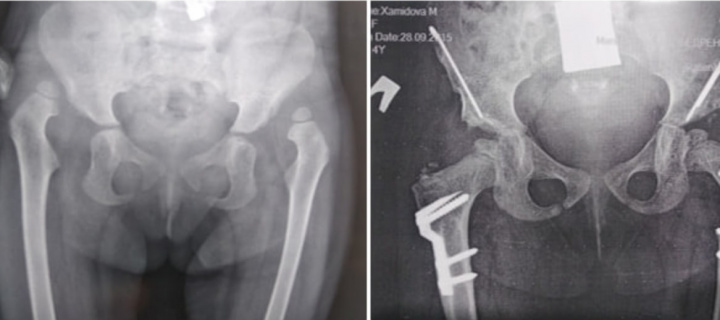

Ўзбекистонда болалар жарроҳлигига оид янги усул патентланди